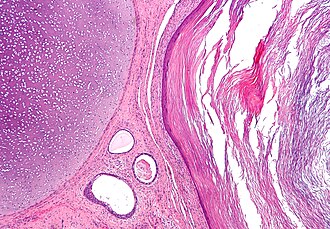

Template:Px Mature teratoma. H&E stain. | |

| LM | classically all three germ layers: ectoderm (skin, (mature) CNS), mesoderm (muscle, bone, connective tissue, blood), endoderm (internal organs) |

Features - three germ cell layers (usually):[6]

- Ectoderm:

- Skin, (mature) CNS.

- Mesoderm:

- Muscle, bone, connective tissue, blood.

- Endoderm:

- Internal organs.